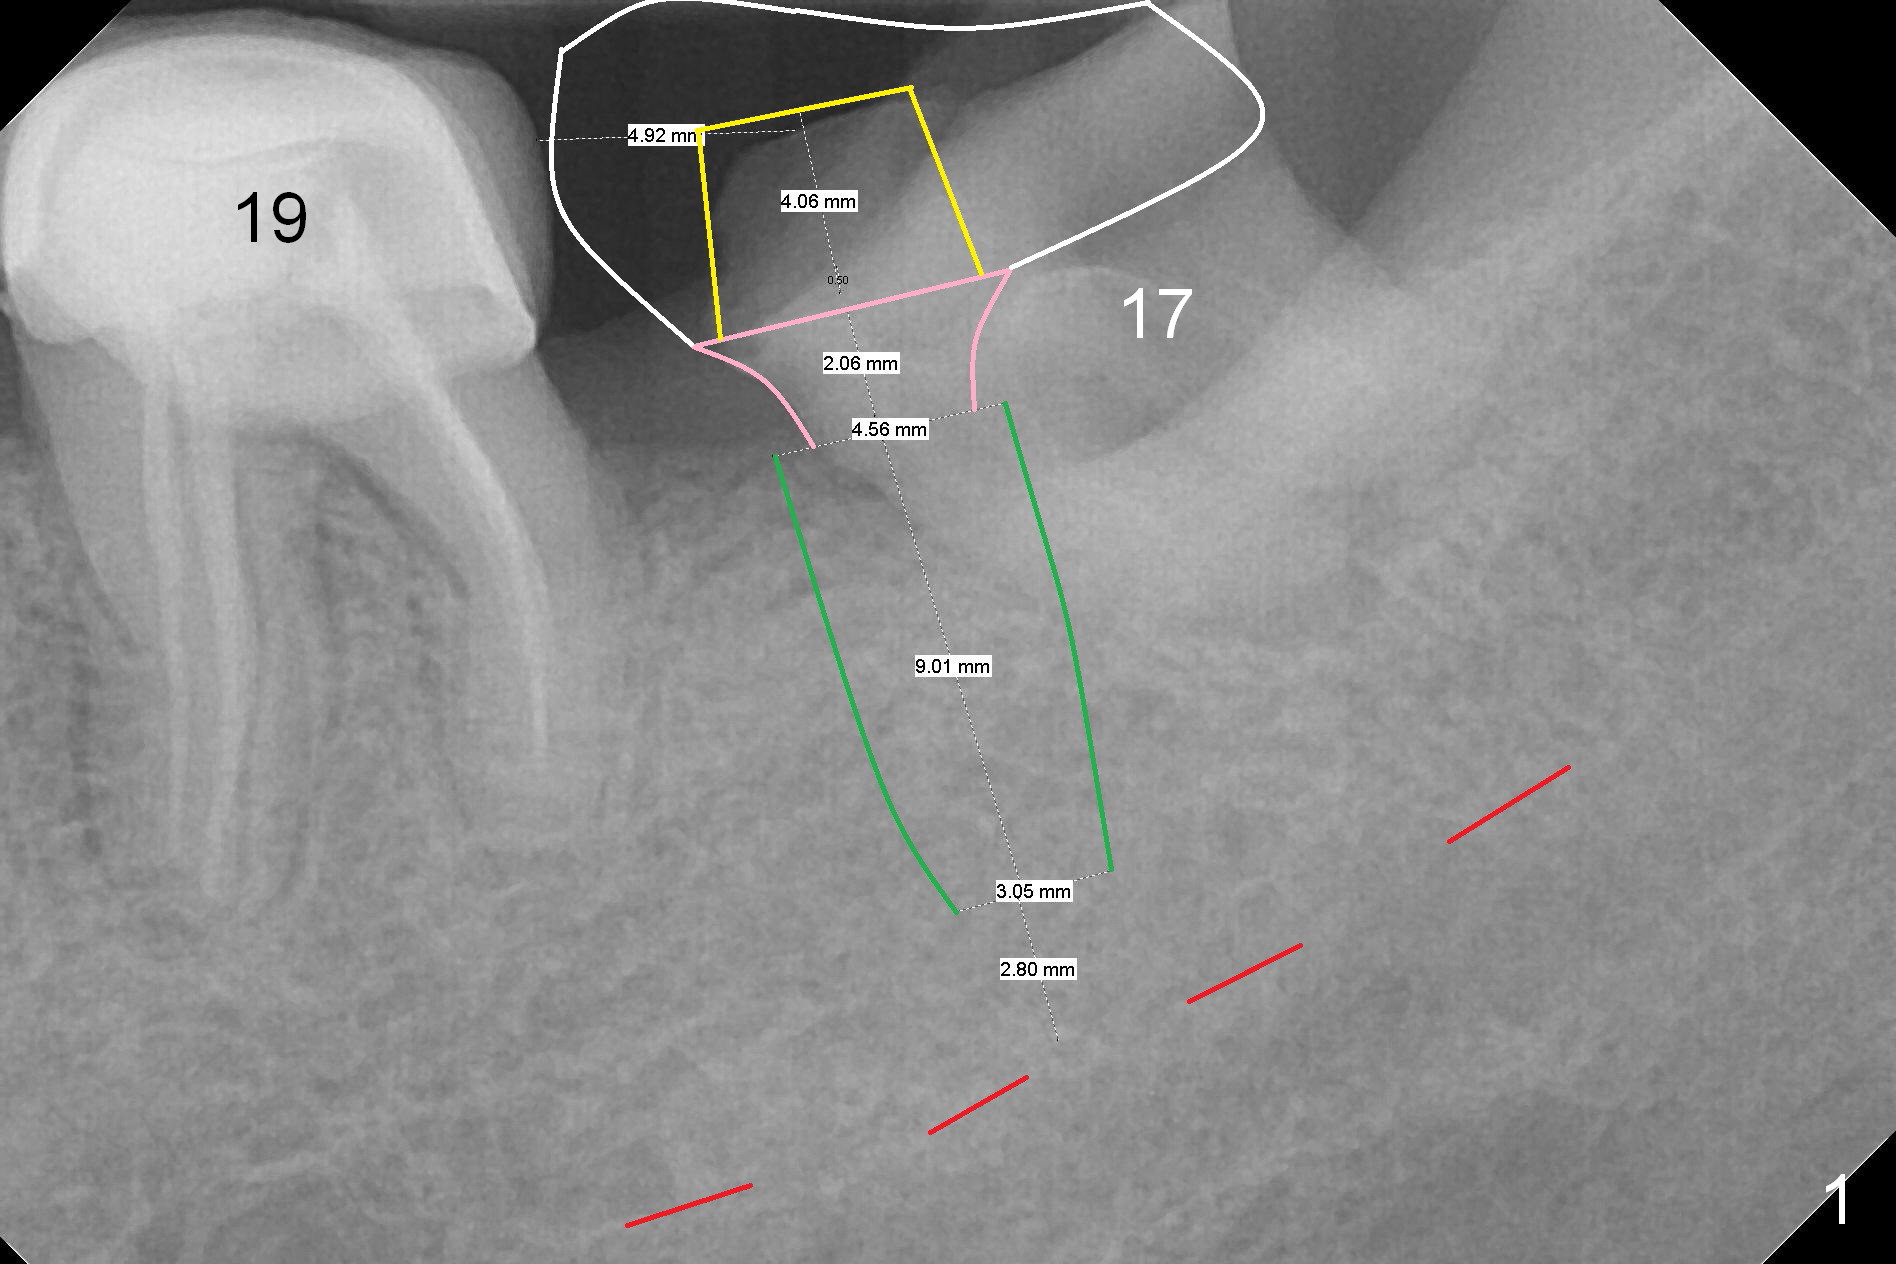

A 47-year-old woman is going to have an implant for #18 (Fig.1).   Since the tooth #17 has migrated mesially so much that the implant will be placed in the mesial socket of the tooth #17 (green area) immediately after extraction (no antibiotic).  After immediate placement of an abutment (yellow and pink), an immediate provisional will cover the sockets of #17 (white).